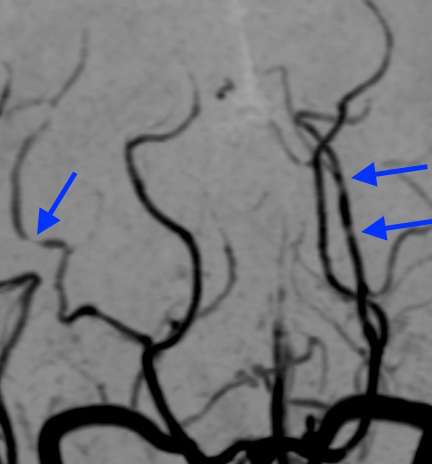

さらに、MRA検査で血管を見たところ、

脳血管の所々に、くびれて細くなった部分が見られています。そして、この画像所見から可逆性脳血管攣縮症候群と診断しました。